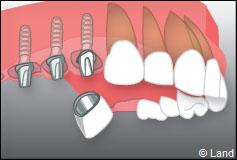

Exemple de 3 dents manquantes remplacées par 3 couronnes sur implants.

Pose des piliers prothétiques et des 3 couronnes scellées.

– le remplacement de plusieurs dents manquantes par un bridge sur implants. Cela évite l’appareil amovible.